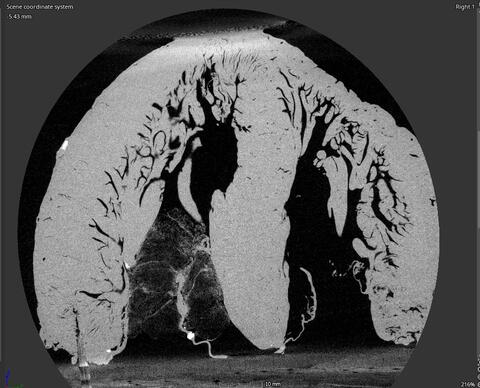

Within the human heart are numerous small muscle bundles called the trabeculae carneae. Despite their significance to the heart’s anatomy, their function is not well understood and most models of the heart ignore them.

As people grow older, heart muscles can grow stiff, reducing efficiency and sometimes resulting in untreatable diastolic heart failure. SwRI and UTSA are scanning cadaver hearts using a powerful computer tomography (CT) scanner at SwRI to inform a potential new surgical intervention.

“Capturing the intricate structures of the trabeculae carneae requires something more powerful than an MRI or standard CT scanners,” Bartels said. “We’ll utilize a micro-focus X-ray CT scanner here at SwRI to create images of explanted human hearts.”

The images of the heart’s intricate inner structures will help Han to create a realistic anatomical model of the trabeculae carneae, building on a previous model he developed for the left ventricle.